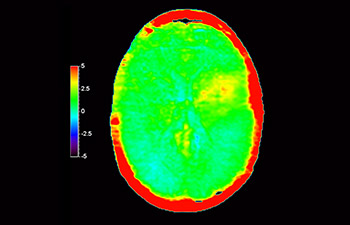

z użyciem metody 3D APT